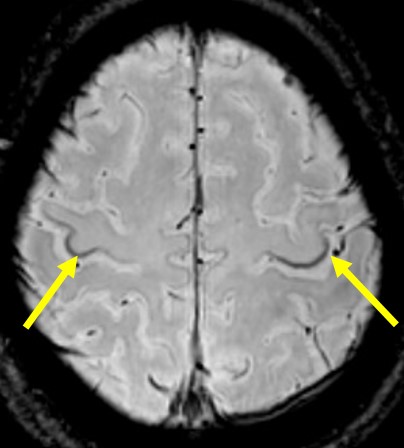

筋萎縮性側索硬化症(ALS) 筋萎縮性側索硬化症(ALS)

PADRE(位相差強調画像)での SWI(磁化率強調画像)での運動皮質

Zebraサイン の低信号